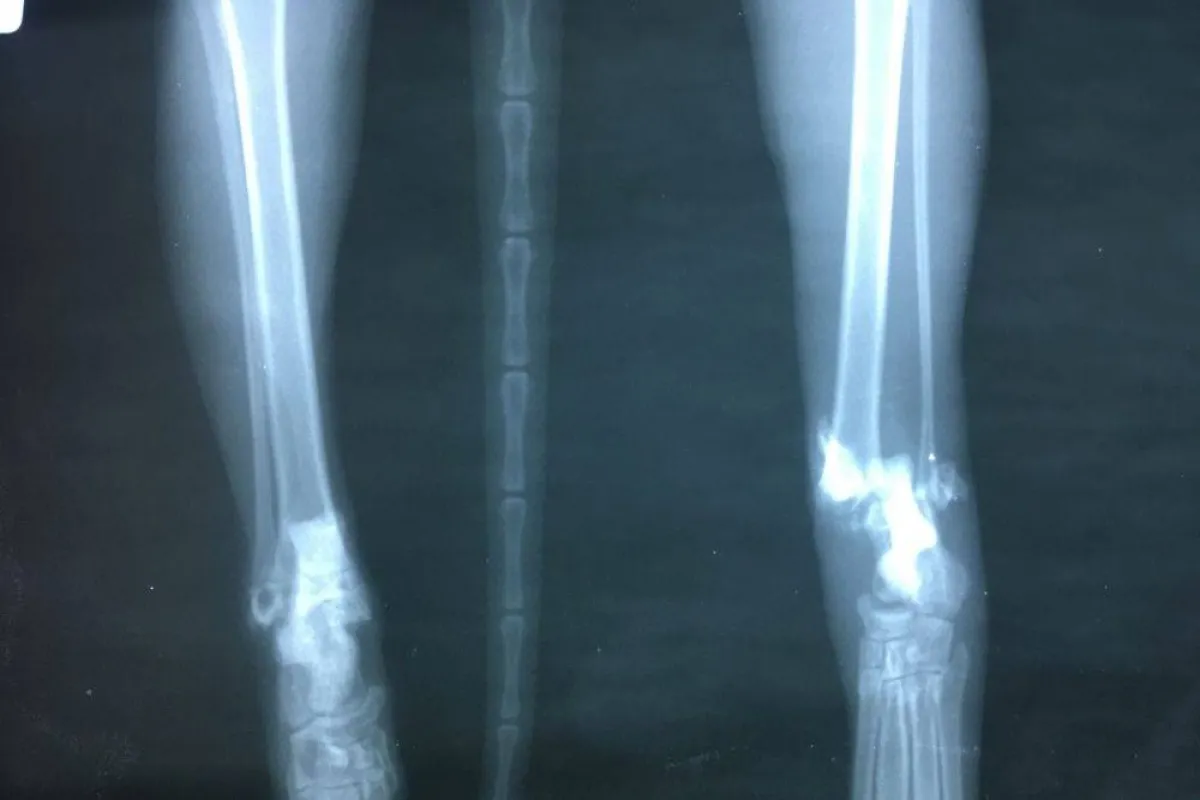

عبارة عن كيفية استعمال كربونات الكالسيوم الموجودة في الصدف ومواد عضوية أخرى لصنع هيكل للعظام الصناعية بديل آمن لأسياخ الحديد وكل ما يتم وضعه بديلا للعظام المكسورة في جسم الإنسان والتي لا يستطيع الجسم إصلاحها بمفرده وبشكل طبيعي.

يساعد هذا الهيكل المصنع من مركبات الكالسيوم الموجودة في الصدف بشكل كبير على تقليل الآثار السلبية التي تؤثرها الأسياخ في جسم الإنسان كالصدأ والالتهابات المؤلمة التي تسببها بدائل العظام المصنعة من الحديد وغيرها من المواد الكيميائية الأخرى.